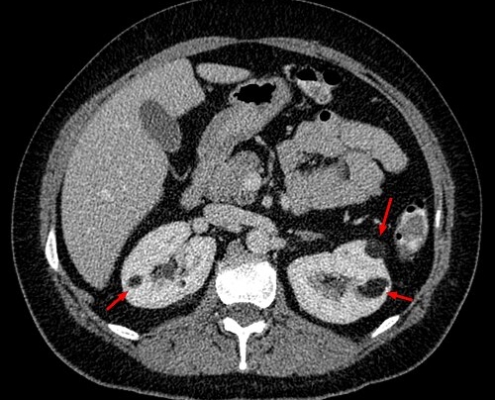

Managing Kidney, Bladder, and Prostate Health

Taking care of your kidney, bladder, and prostate health is important…